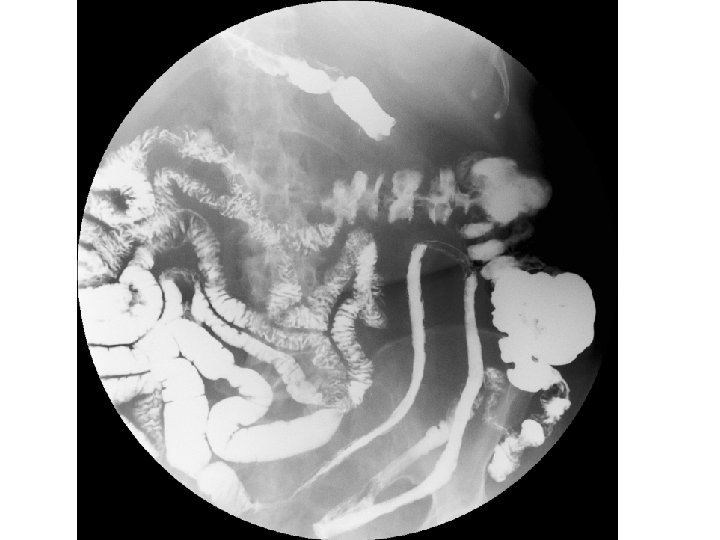

ESTUDIO BARITADO

Estudio baritado (I) • La distribución segmentaria coincidiendo con territorios vasculares concretos, con indemnidad de otros territorios, y el aspecto "en asa" (literalmente) en el caso delgado, con extensión de concavidad a concavidad, orientan al diagnóstico de isquemia crónica segmentaria cuando se realiza un estudio baritado.

Estudio baritado (I) • En nuestra paciente se daban estos hallazgos: – distribución segmentaria y única; – aspecto "en asa" con extensión de concavidad a concavidad; – preservación del íleon terminal.